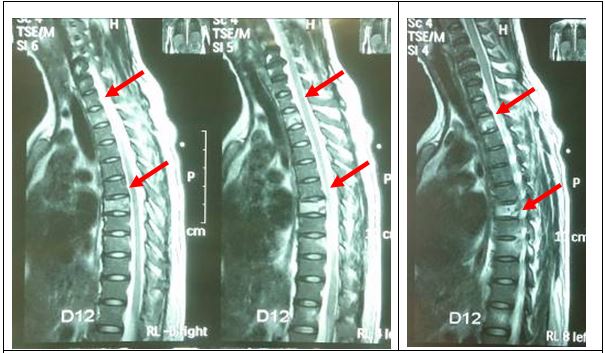

Chụp cộng hưởng từ cột sống: Tổn thương phá hủy xương D2, D7, D9 và tổn thương cung sau xương sườn tương ứng

Hình 3: Hình ảnh cộng hưởng từ cột sống: Tổn thương phá hủy xương D2, D7, D9, tổn thương cung sau xương sườn tương ứng